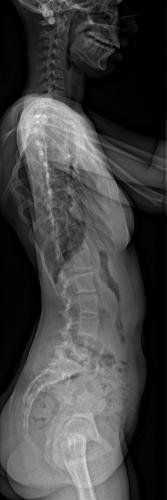

Images de scolioses opérées 16 janvier 202418 janvier 2023 par Damien Scoliose Thoracique et lombaire 1 Radio pré-opératoire de Face Radio pré-opératoire de Profil Radio à 1 an de recul de Face Radio à 1 an de recul de Profil